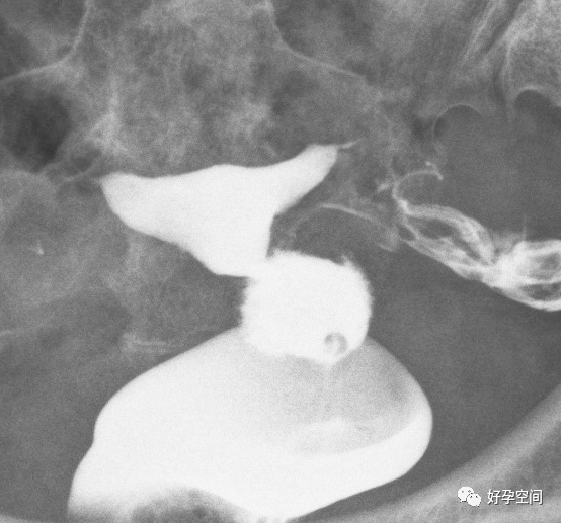

输卵管走行僵硬,形态固定,没有变化,伞端粘连,少许造影剂溢出

弥散相,双侧输卵管内见较多造影剂残留影